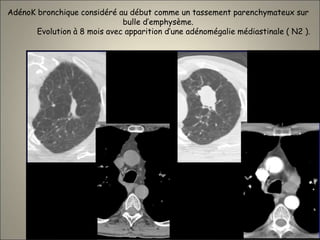

AdénoK bronchique considéré au début comme un tassement parenchymateux sur

bulle d’emphysème.

Evolution à 8 mois avec apparition d’une adénomégalie médiastinale ( N2 ).